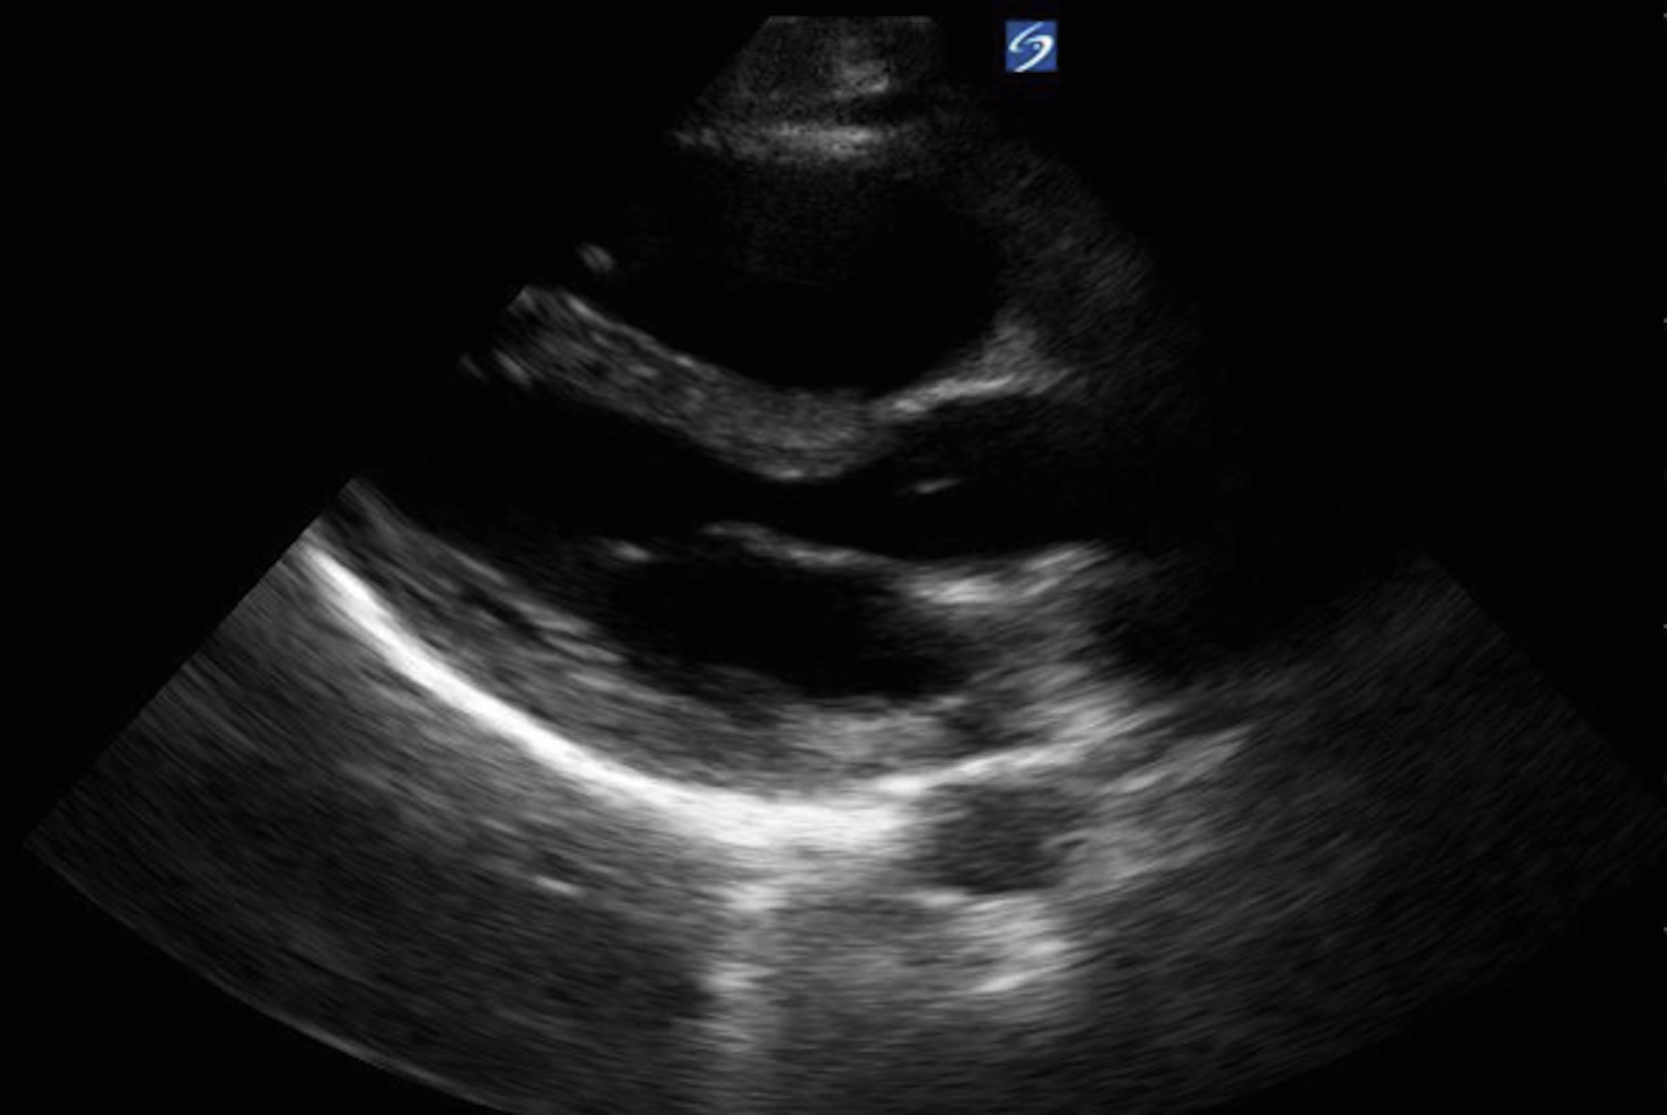

Image Acquisition

Cardiac US is performed through the transthoracic and transabdominal windows with the use of small curvilinear or phased array transducers. Typical views include the subcostal four-chamber view (subxiphoid), parasternal long-axis view ( Fig. e3.10 ; see Video e3.4 ), parasternal short-axis view, and apical four-chamber view. The subcostal four-chamber view, as in the FAST, is ideal for assessment of pericardial effusion and useful during cardiac arrest because it does not interfere with chest compressions. The long-axis subcostal view highlights the inferior vena cava (IVC) and can indicate volume status. The parasternal views are excellent windows for LV assessment. The apical four-chamber view is ideal for comparison of RV and LV sizes and function. Several US protocols have been developed to evaluate undifferentiated hypotension and can be used to narrow the differential diagnosis.

Normal parasternal long-axis view of the heart.